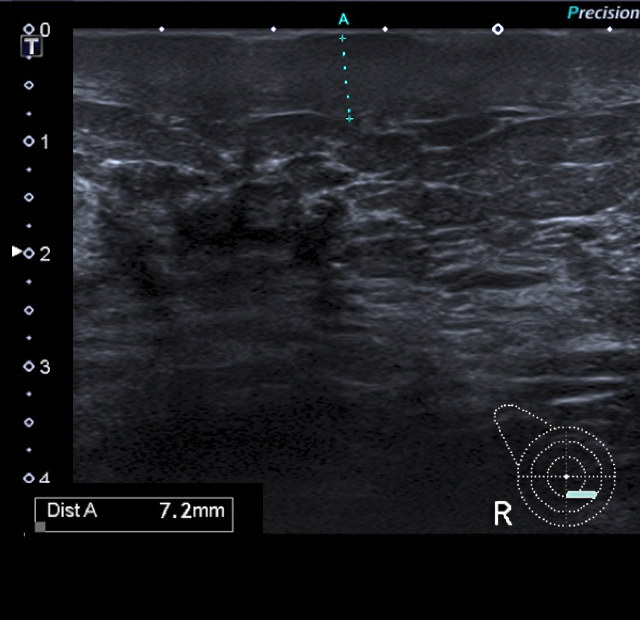

1. ¿Cuál sería tu informe radiológico de la mamografía y ecografía y qué recomendarías?

- A. Estudio dentro de la normalidad (BI RADS 1). Controles habituales.

- B. Cambios morfológicos en MD en relación con sus antecedentes, estable con respecto a control previo (BI RADS 2). Control anual.

- C. Cambios morfológicos en MD en relación con sus antecedentes, con engrosamiento cutáneo en cuadrantes inferiores (CCII) de MD (BI RADS 3). Control mamográfico y ecográfico en 6 meses.

- D. Cambios morfológicos en MD en relación con sus antecedentes, con engrosamiento cutáneo en CCII de MD de nueva aparición (BI RADS 4). Se recomienda biopsia cutánea (punch).

- E. Distorsión espiculada con microcalcificaciones en plano posterior de cuadrantes superiores (CCSS) de MD sospechosa de malignidad (BI RADS 5). Se recomienda biopsia con aguja gruesa (BAG).